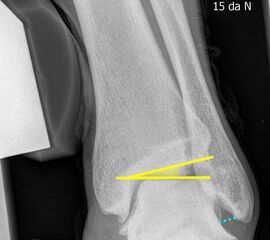

Sprunggelenk lateral ohne Belastung

Positionierung:

• Patient liegt auf dem Rücken und dreht den Fuß des aufzunehmenden Beins so nach innen, dass beide Malleolen genau übereinanderstehen.

• Die laterale Fuss-Seite liegt auf der Kassette, das Sprunggelenk ist 90° angewinkelt.

• Der Zentralstrahl wird zentral auf das Sprunggelenk gerichtet.

Kennzeichen des Röntgenbildes:

• Oberes und unteres Sprunggelenk sind rein seitlich abgebildet, inklusive Kalkaneus.

• Die Malleolen kommen übereinander zu liegen.

• Tibiagelenkfläche und Talusrolle werden exakt seitlich dargestellt, es kommt zu keinen Doppelkonturen.

• Die Fibula projiziert sich ins mittlere bis hintere Drittel der Tibiagelenkfläche.

• Die vordere und hintere Tibiakante, das Chopart-Gelenk und das Subtalargelenk kommen zur Darstellung.

• Das proximale Ende des Os metatarsale V ist mit abgebildet.

• Der Weichteilmantel (Achillessehne) ist erkennbar.

Besondere Bemerkungen zum Beispielbild:

• Patient mit anamnestisch chronischer OSG Instabilität.

• Ventral der Tibia findet sich ein abgebrochener Osteophyt.

Zur Vollansicht und zum Lesen der Bildbeschreibung bitte die Bilder anklicken.